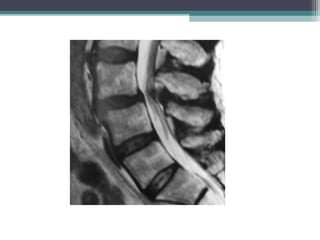

• Muestran una hidromielografía de la columna lumbar con

espondilolistesis L4 y discartrosis L5 severa que condicionan un

canal lumbar estrecho.